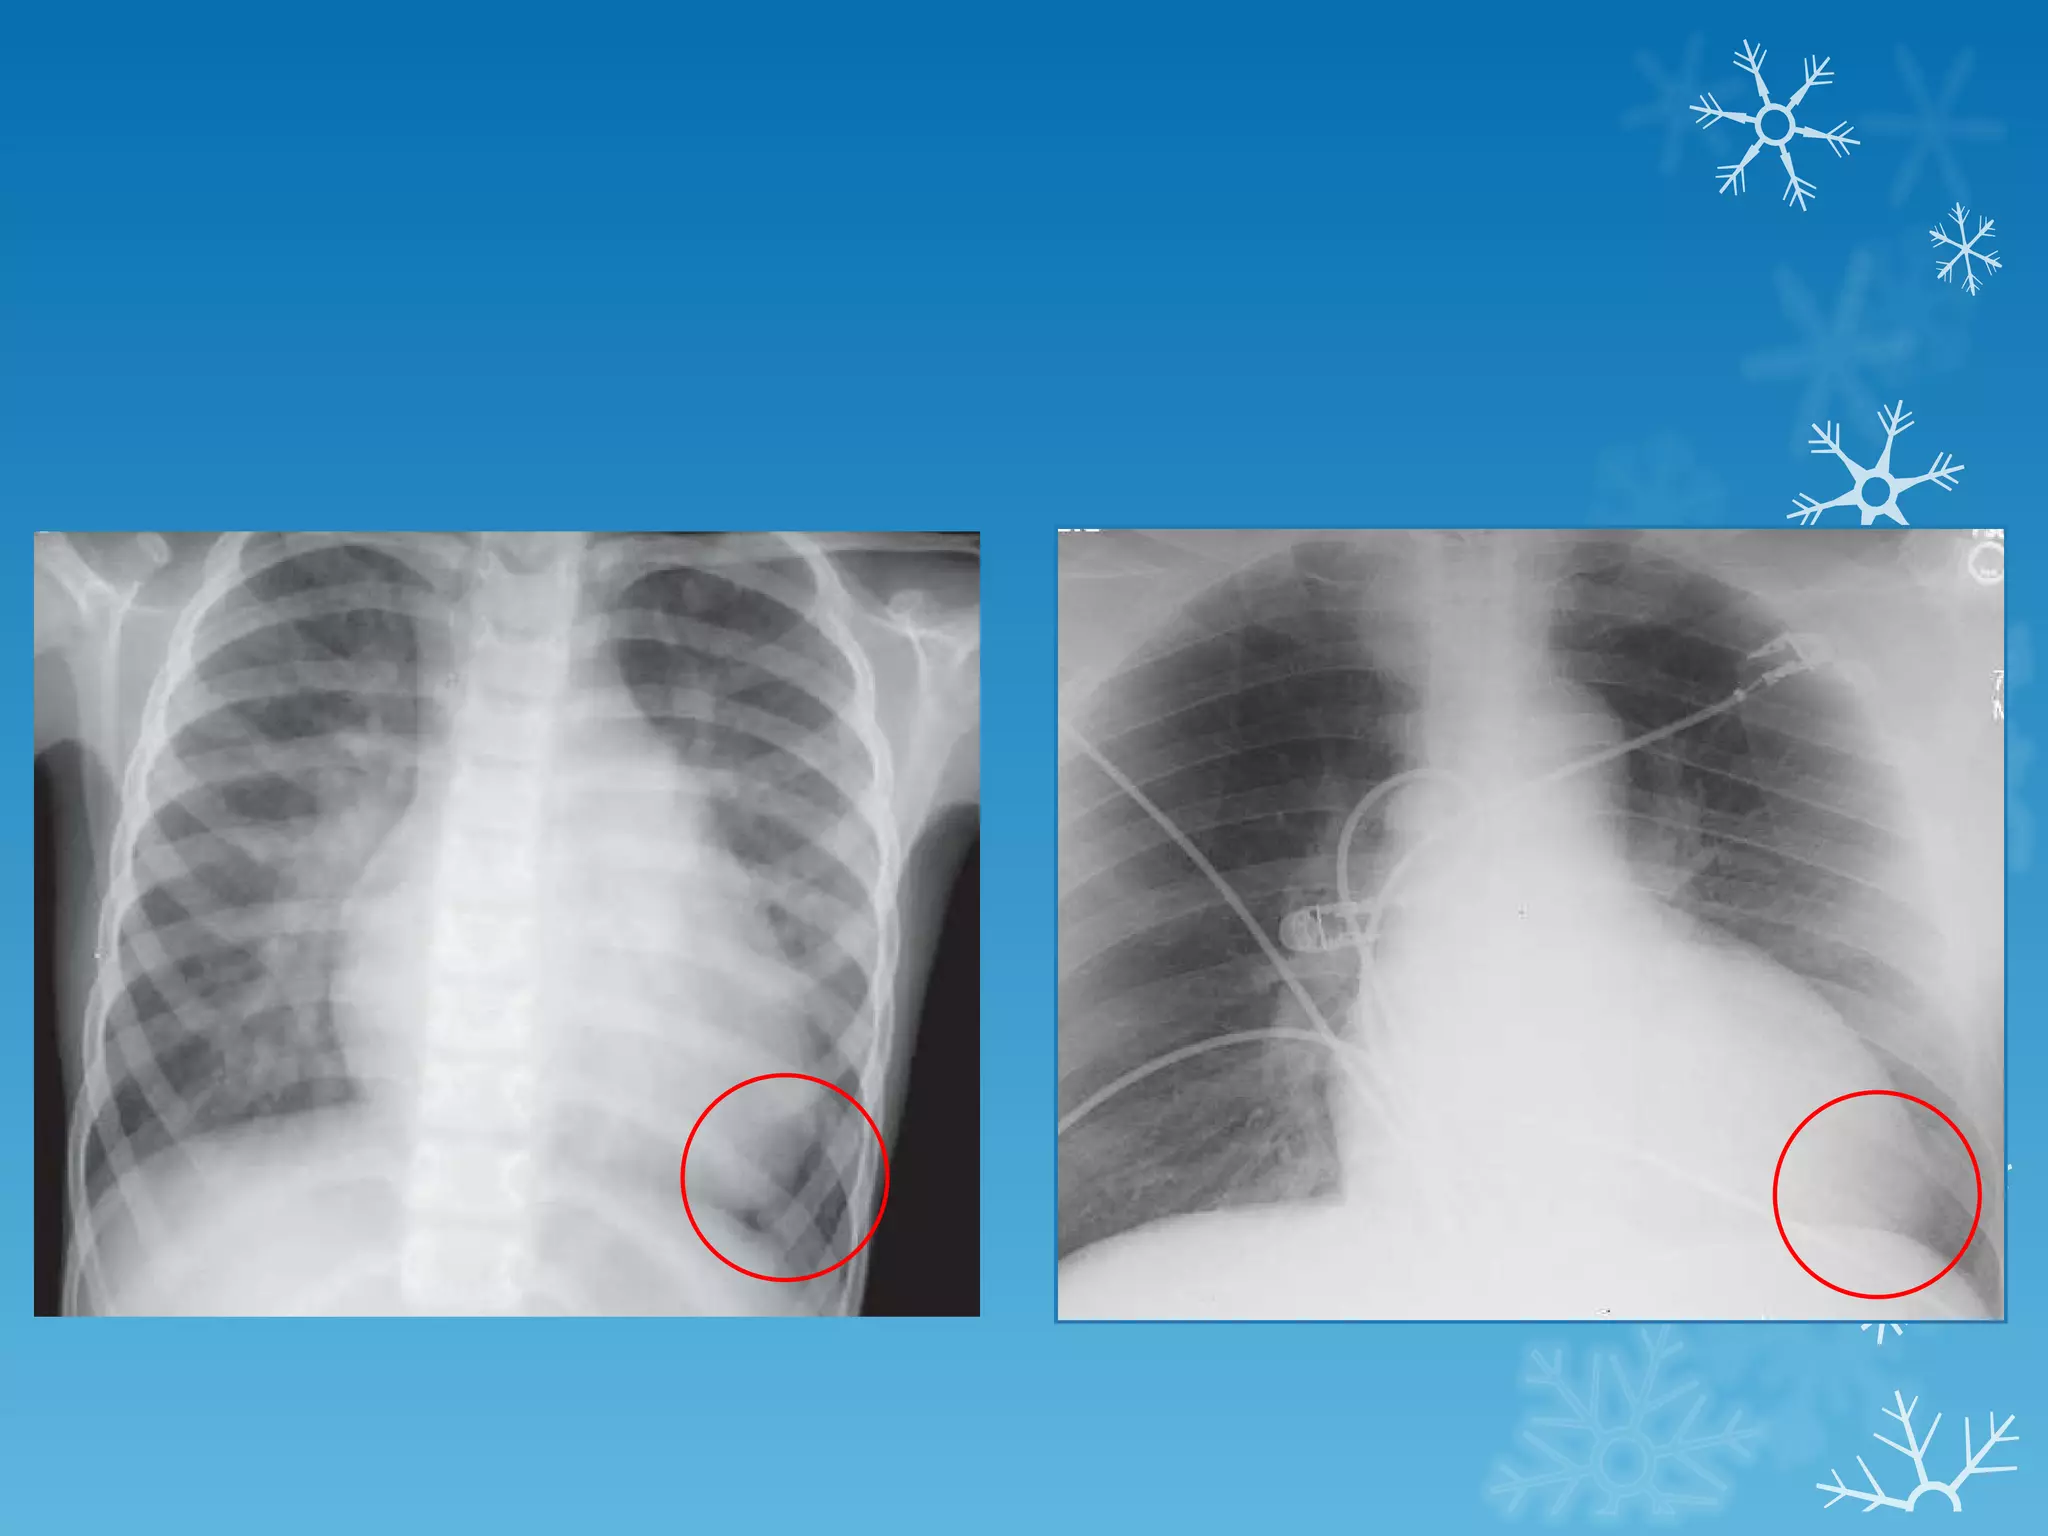

This document discusses chest x-ray interpretation and provides guidance on evaluating x-rays. It explains that tissue density determines how an x-ray beam penetrates, with denser tissues appearing whiter and less dense tissues appearing blacker. It also outlines different chest x-ray views and factors to consider like patient orientation, age, gender, and rotation. Abnormalities are described as appearing too white, too black, too large, or in the wrong place. The document stresses a systematic approach of identifying, localizing, describing lesions, and providing differential diagnoses.